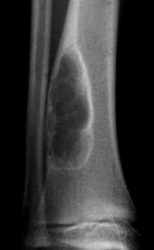

Fig 96. Defecto fibroso cortical.

A: Rx AP y B: Rx lateral. Lesión metafisiaria, de bordes escleróticos, secundaria a regresión de un defecto fibroso cortical.